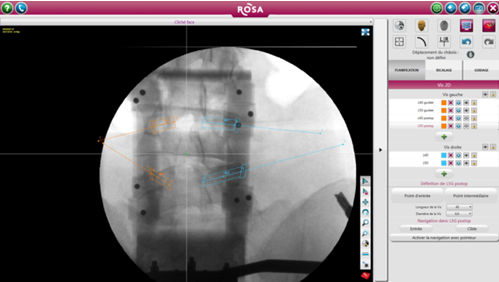

ROSA 是一种影像导航设备,直接根据术中放射线图像上确定的标志或使用导航指针定位工具。引导是基于术中2D图像处理软件完成的轨迹规划,随后患者俯卧位完成注册(图1)。在手术开始时,沿着患者的右手边放置机器人,确保机器人的手臂能充分地覆盖两个节段(图2)。然后外科医生站在患者的另一边。手术室的组织结构图如图3所示。

图1术前X线透视下椎弓根螺钉的规划